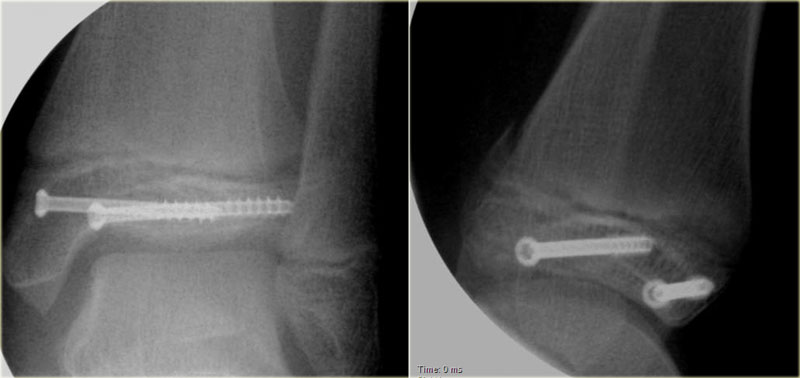

Study the images and then continue reading.

Triplane fracture Triplane fracture

At first this looks like a Weber B fracture with an oblique fracture in the fibula as seen on the lateral view (black arrows).

Notice however that this fracture line stops at the level of the epiphyseal plate.

So this is the fracture of the metaphysis in the coronal plane.

On the AP-view there is a lucency within the epiphysis, which is the epiphyseal fracture in the sagittal plane.

Notice also that the medial epiphysis is already closed, while the lateral portion is still open(blue arrows).

We have to assume that there is an epiphysiolysis of this lateral portion.

Here another example.

There is only a small metaphyseal fragment, which is usually the case (red arrow).

The fracture through the epiphysis is indicated by the blue arrow.